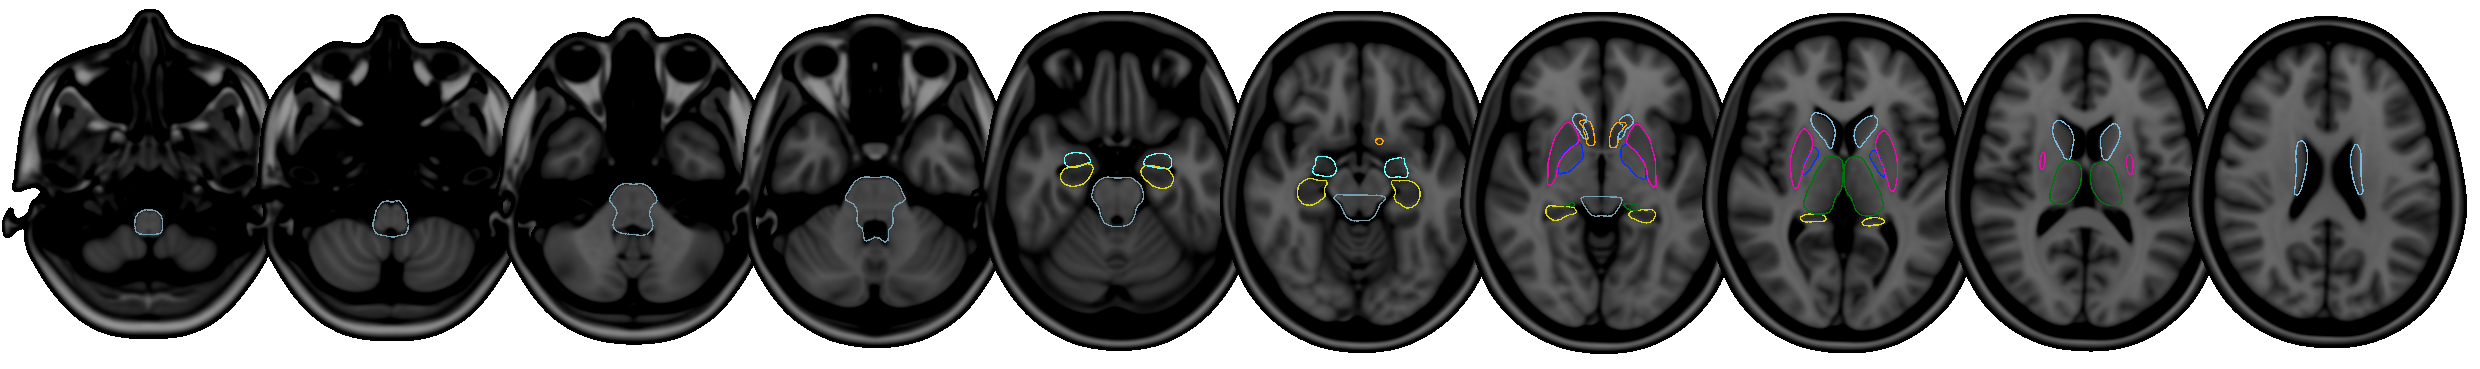

FIRST is a model-based segmentation/registration for automatic segmentation of a number of subcortical structures.

The supported structures are listed below. To segment these structures, FIRST needs a good quality T1-weighted image:

- Putamen (

Puta) - Caudate nucleus (

Caud) - Nucleus accumbens (

Accu) - Globus pallidus (

Pall) - Hippocampus (

Hipp) - Amygdala (

Amyg) - Thalamus (

Thal) - Brainstem (

BrStem)

The shape/appearance models used in FIRST are constructed from manually segmented images provided by the Center for Morphometric Analysis (CMA), MGH, Boston. The manual labels are parameterized as surface meshes and modelled as a point distribution model. Deformable surfaces are used to automatically parameterize the volumetric labels in terms of meshes; the deformable surfaces are constrained to preserve vertex correspondence across the training data. Furthermore, normalized intensities along the surface normals are sampled and modelled. The shape and appearance model is based on multivariate Gaussian assumptions. Shape is then expressed as a mean with modes of variation (principal components). Based on our learned models, FIRST searches through linear combinations of shape modes of variation for the most probable shape instance given the observed intensities in a T1-weighted image.

The structures that FIRST can segment are listed below. The Abbrevbiated name column gives the name that you should pass to the FIRST command-line tools when you want to segment a specific structure. The Integer label column gives the integer label that FIRST assigns to each structure in its output files (e.g. output_*_firstseg.nii.gz). The Modes column gives the recommended number of modes of variation to use for each structure when fitting the subcortical model (note that this is normally taken care of automatically for you).

| Structure | Abbreviated name | Integer label | Modes |